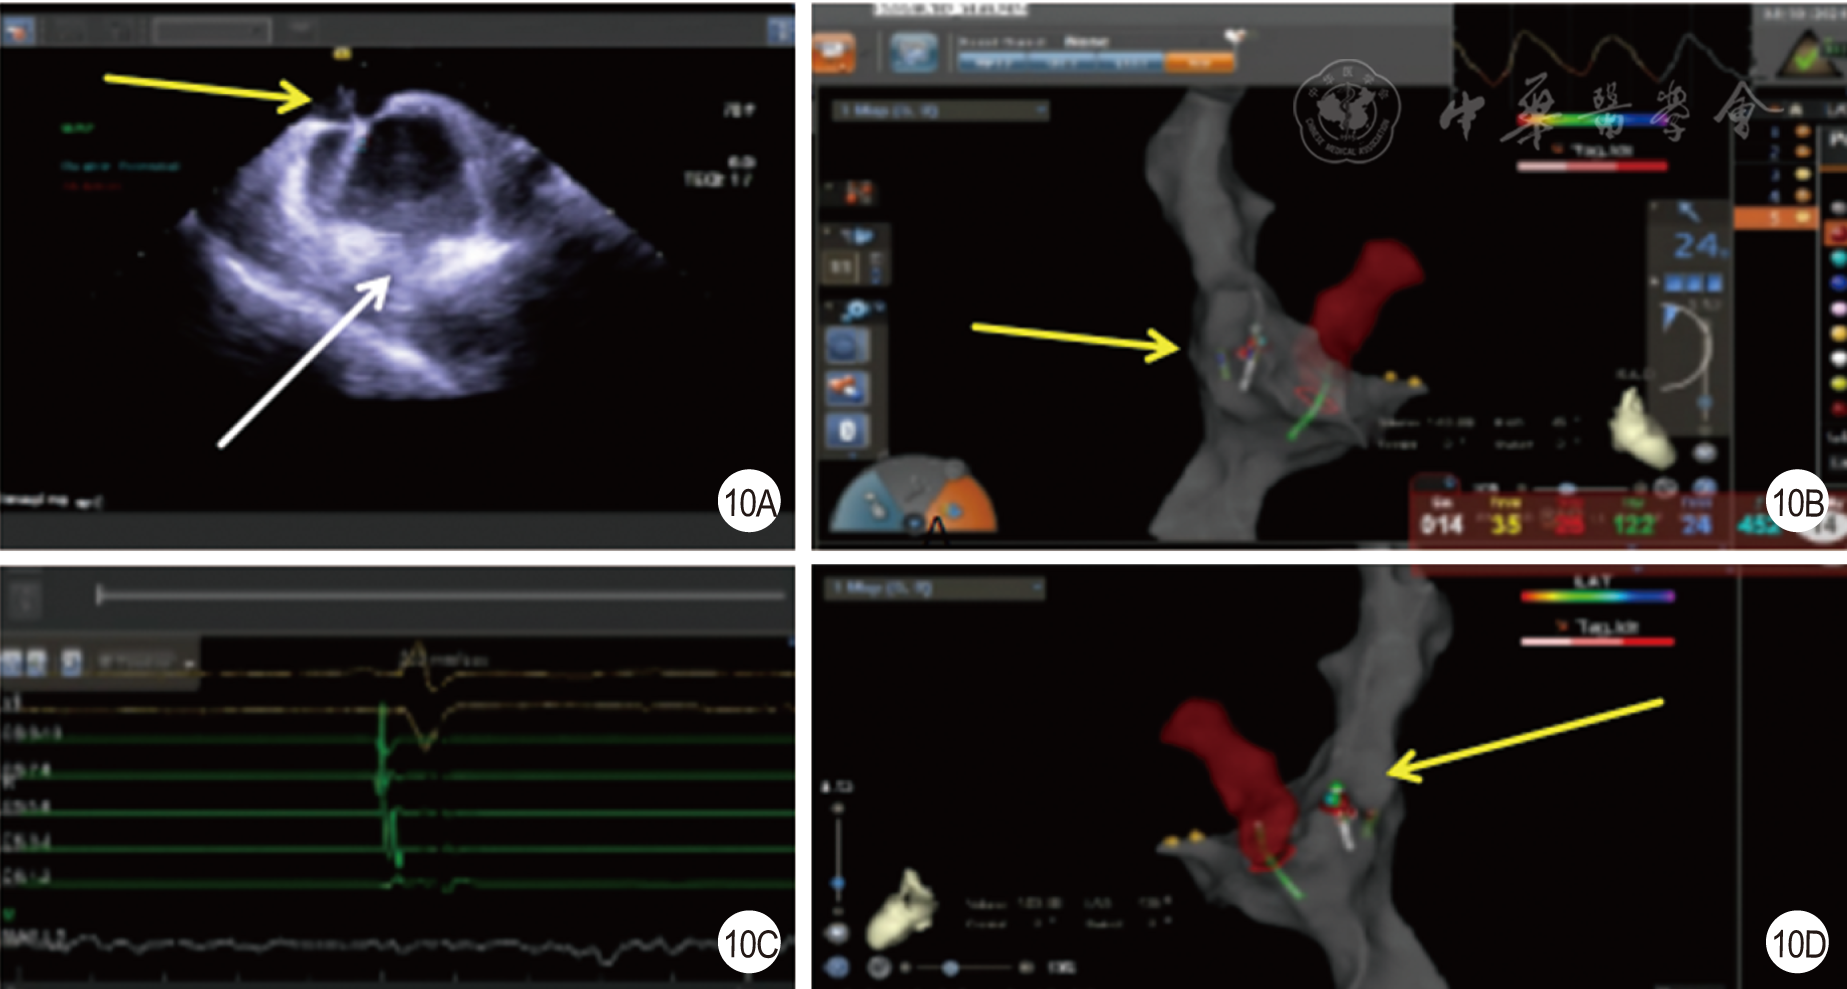

图10 易化心腔内超声心动图联合全三维穿刺房间隔[10A为穿刺靶点(黄色箭头)及导管指向肺静脉和华法林嵴(白色箭头);10B为右前斜30°导管消融穿刺靶点;10C为导管电位很小;10D为左前斜135°显示导管消融穿刺靶点]